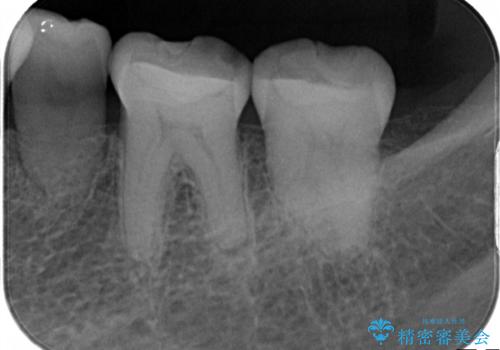

- 以前治療したところがしみて、アイスが食べられないから被せものの治療をしてほしいと来院された患者様です。

咬合が強く、歯牙にマイクロクラックが入っている状態でした。歯髄は保存可能と診断され、フルジルコニアクラウンによる治療を行いました。

咬合面に広範囲の修復物がある状態で中心に強い力が加わると歯牙は外方性の歪みが生じ、マイクロクラックができます。これを防ぐには、咬頭被覆するアンレー、もしくはクラウンによる治療が必要です。